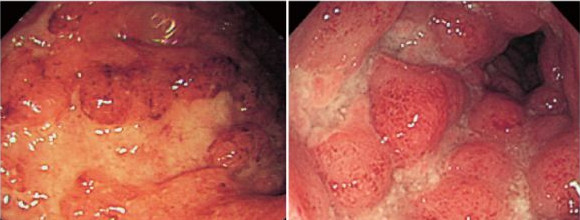

以下为炎症性肠病的两组内镜图谱:

Crohn病的纵行溃疡

A图:溃疡边缘不规则

B图:周围粘膜伴随有黄白色的水肿状炎型息肉

溃疡性肠炎的纵行溃疡

A图:溃疡大多较浅并且边缘不规则

B图:周围粘膜呈不规则的红色颗粒状,还伴随有表面不规则的炎型息肉。类似与Crohn病症里看到的鹅卵石状的样子,所不同的是表面有颗粒状的红点。